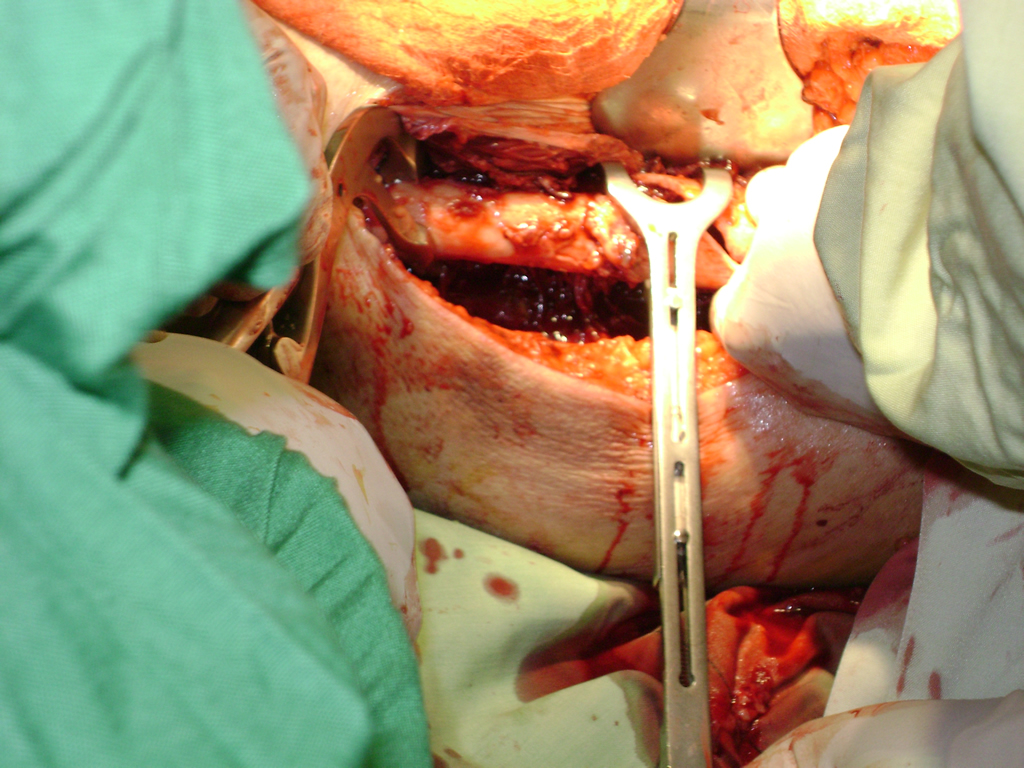

Cirugías de Quiste de Baker

La cirugía de fractura de cadera se realiza para reparar una ruptura en la parte superior del hueso del muslo. Este hueso se denomina fémur.

Es parte de la articulación coxofemoral. Si una fractura de cadera no recibe tratamiento, es posible que deba permanecer en una silla o en la cama.